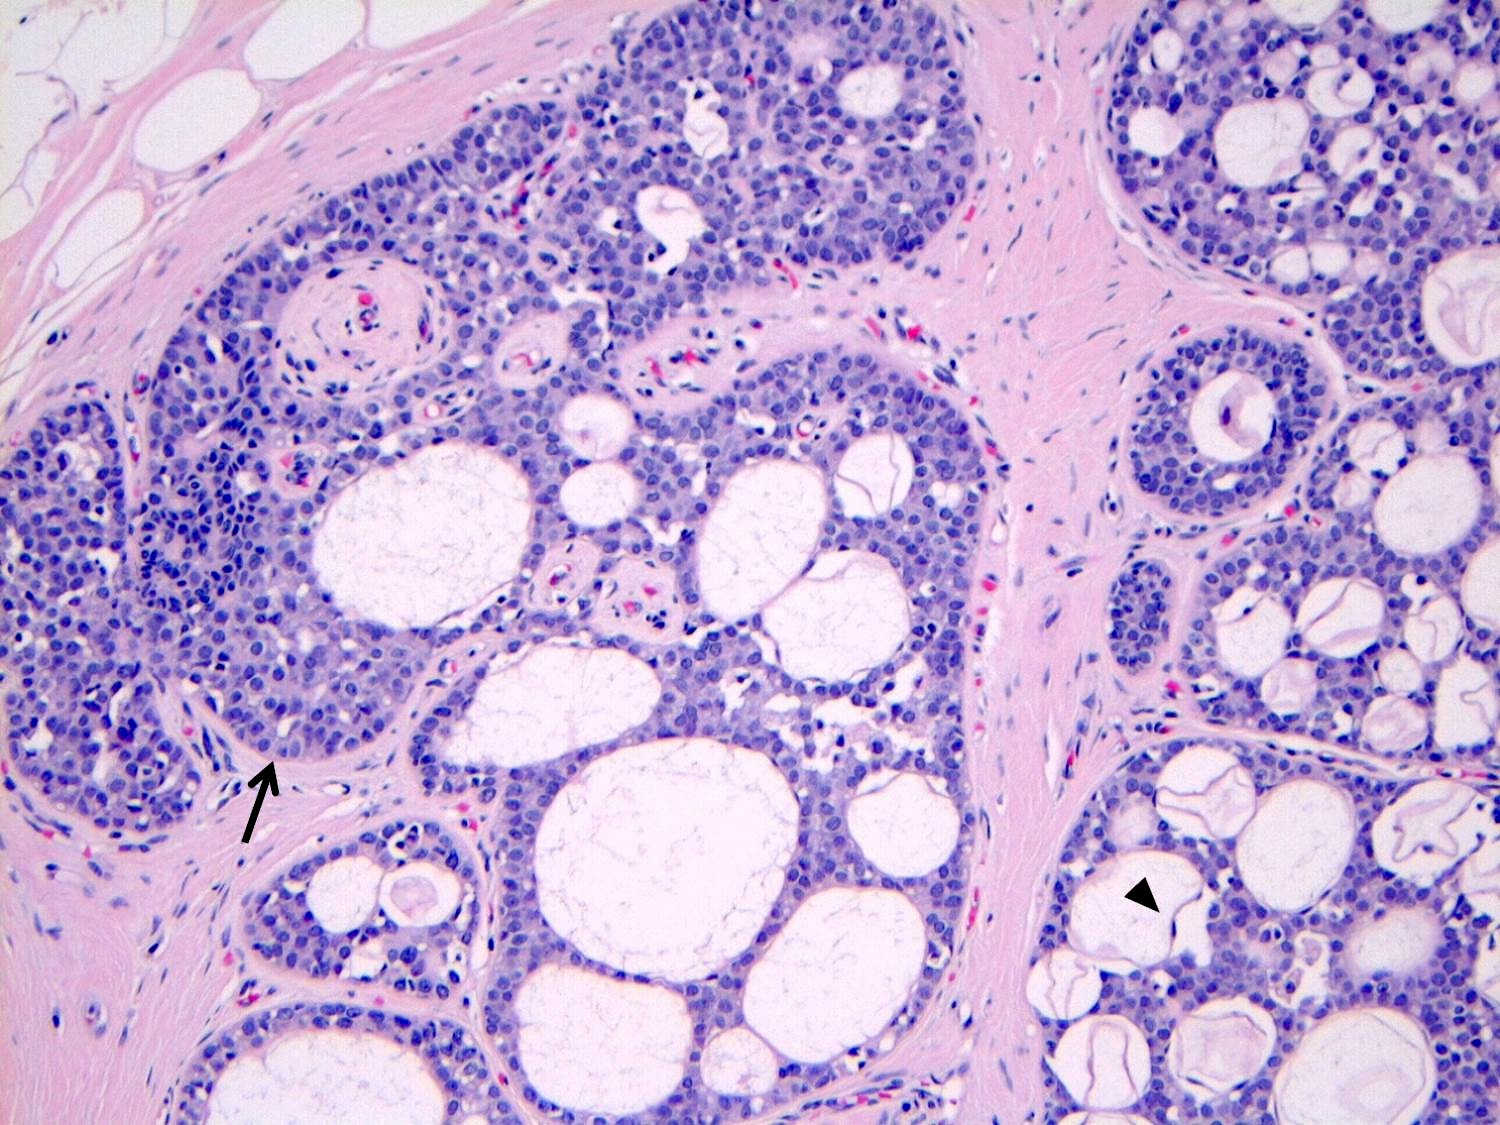

Microscopic (histologic) description

- LCIS involves the terminal duct lobular unit (TDLU), filling and distending acini

- > 50% of the acini in a TDLU must be filled and expanded to qualify as LCIS; otherwise, called atypical lobular neoplasia

- Lobular distention is defined as the presence of ≥ 8 cells in the cross sectional diameter of an acinus

- LCIS may secondarily involve (or arise in) sclerosing adenosis, radial scar, fibroadenoma, collagenous spherulosis or papilloma

- Classic LCIS cells are monomorphic, evenly spaced, loosely cohesive and do not show polarization or gland formation

- Type A: nuclei are small to slightly enlarged (1 - 1.5x size of lymphocyte) with uniform round nuclei and inconspicuous nucleoli

- Type B: nuclei larger (2x size of lymphocyte), more abundant cytoplasm and more prominent nucleoli

- Type A and B cells can coexist in the same lesion

- Cytoplasm of LCIS cells is typically pale to lightly eosinophilic with indistinct cell borders

- In almost all cases of LCIS, at least some cells contain intracytoplasmic vacuoles or lumina, which may contain an eosinophilic globule; this feature is not specific to LCIS

- Vacuoles may be subtle such that special histochemical stains for mucin are required in order to demonstrate; alternatively, they may be large enough to push the nucleus against the cell membrane and produce signet ring cell forms

- Outer layer of myoepithelial cells is retained in the acini and ducts involved but it may be attenuated

- In some cases, scattered myoepithelial cells can be admixed with the neoplastic epithelial cells within the involved spaces

- Classic LCIS does not show significant nuclear pleomorphism or mitosis

- Classic LCIS may rarely display single cell apoptosis or minute foci of necrosis but typically does not show comedo type necrosis

Microscopic (histologic) images

Contributed by Anna Biernacka, M.D., Ph.D.